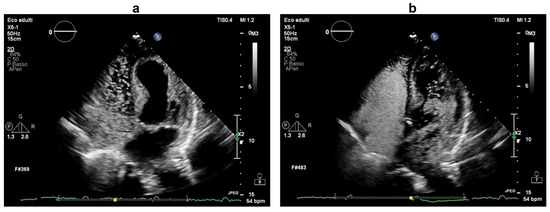

Pitfalls of Using Imaging Technique in the Presence of Eustachian Valve or Chiari Network: Effects on Right-to-Left Shunt and Related Influencing Factors

by Han Zhang, Weiwei Liu, Jie Ma, Huanling Liu, Lin Li, Jinling Zhou, Shanshan Wang, Shanshan Li, Wei Wang and Yueheng Wang

Diagnostics 2022, 12(10), 2283; https://doi.org/10.3390/diagnostics12102283 - 21 Sep 2022

When patent foramen ovale (PFO) combines with the prominent Eustachian valve or Chiari network (EV/CN), contrast transthoracic echocardiography (cTTE) may miss the diagnosis of PFO. We sought to determine the characteristics of right-to-left shunt (RLS) in PFO patients with prominent EV/CN on cTTE [...] Read more.

When patent foramen ovale (PFO) combines with the prominent Eustachian valve or Chiari network (EV/CN), contrast transthoracic echocardiography (cTTE) may miss the diagnosis of PFO. We sought to determine the characteristics of right-to-left shunt (RLS) in PFO patients with prominent EV/CN on cTTE and identify the causal factors of missed diagnosis. We consecutively enrolled 98 patients who suffered from PFO-related stroke and with prominent EV/CN. All patients were divided into the delayed and non-delayed groups according to the characteristics of RLS on cTTE. The characteristics of RLS were compared with those of 42 intrapulmonary shunt patients. The anatomical characteristics of PFO and EV/CN were analyzed in the 98 PFO patients. Upon cTTE, significantly delayed occurrence and longer duration of the RLS in the delayed group were found both at rest and during the Valsalva maneuver, similar to the intrapulmonary shunt. Multivariate logistic analysis revealed that the length of EV/CN (>19 mm) and the diameter of PFO at the left atrium aspect (<1.2 mm) were high-risk factors for missed diagnosis. In conclusion, RLS showed delayed emergence and disappearance in some of the PFO patients with prominent EV/CN. The length of EV/CN and the diameter of PFO may have been related to the missed diagnosis of PFO. Full article